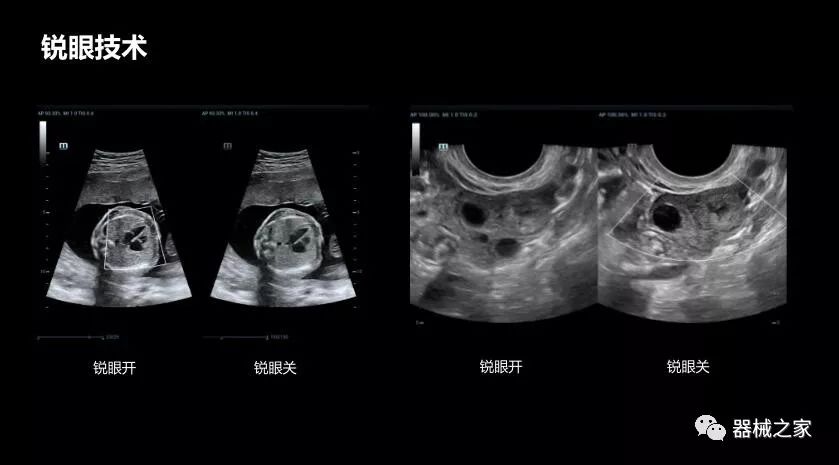

• 銳眼技術

做胎兒心臟檢查的時候,如果是聲窗不好的孕婦,很難看清胎兒心腔 。女媧Resona 8的銳眼技術能很好的優(yōu)化心腔內(nèi)的噪聲,讓胎心結構完美的呈現(xiàn)。